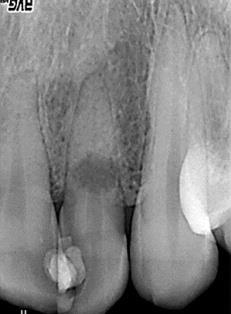

Podczas badania rentgenowskiego (zdjęcie poniżej) w zębie 22 stwierdzono znaczne przejaśnienie w połowie długości kanału korzeniowego. Wskaż prawidłową metodę postępowania: 1) płukanie kanału korzeniowego 0,5-5,25% podchlorynem sodu, naprzemiennie z 30-40% kwasem cytrynowym; 2) płukanie kanału korzeniowego 2% chlorheksydyną; 3) płukanie kanału korzeniowego 5,25% podchlorynem sodu, naprzemiennie z wodą utlenioną; 4) wprowadzenie do kanału korzeniowego nietward- niejącego preparatu wodorotlenku wapnia na okres kilku dni; 5) wprowadzenie do komory zęba watki nasączonej związkiem fenolowym na 48 godzin; 6) wprowadzenie do kanału korzeniowego na okres kilku dni materiału zawierającego jodoform; 7) wypełnienie kanału korzeniowego metodą kondensacji bocznej; 8) wypełnienie kanału korzeniowego z wykorzystaniem technik termoplastycznych. Prawidłowa odpowiedź to: